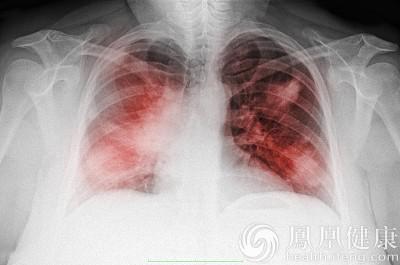

資料圖